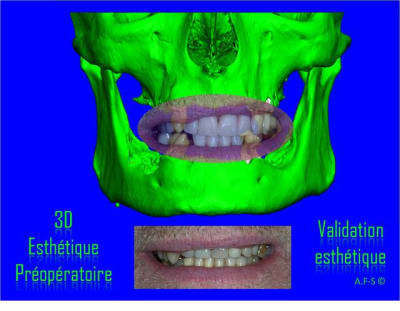

Projet implantaire:

Extraction, pose d’implants Ankylos, pose des piliers Standard définitifs, mise en charge immédiate bi-maxillaire en une chirurgie.

Maxillaire supérieur – extraction 13, 26, 7 implants en MCI, 1 implant en MCR pose summeurs, densification par ostéotme, comblement osseux, bridge provisoire sans fausse gencive avec renfort métallique.

Maxillaire inferieur – extraction 35, 34, 44, 45, 6 implants MCI, comblement osseux, bridge provisoire sans fausse gencive avec renfort métallique.

Le patient présente une perte de DV importante qui doit être corrigé avec les bridges provisoires.

3D

Esthétique

Préopératoire